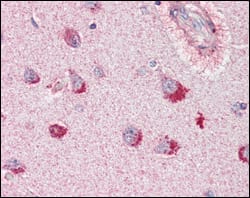

Immunohistochemical analysis of paraffin-embedded human cerebrum tissues using SORL1 mouse mAb with DAB staining.